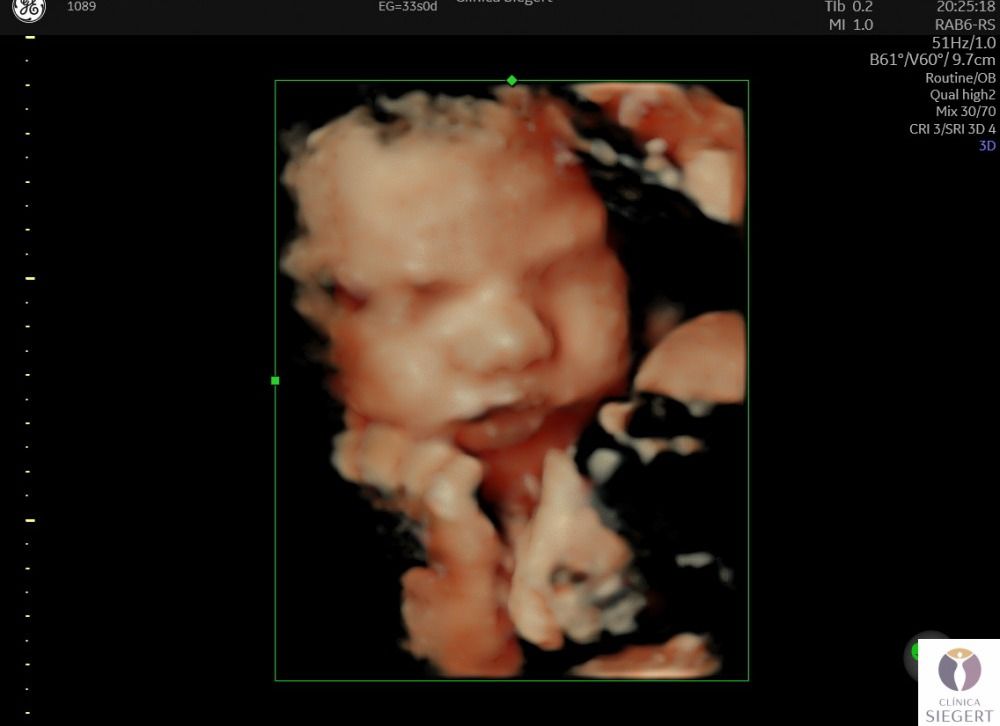

Nuevo ecógrafo de última generación con la mejor imagen 3D 4D 5D (edición en vivo: HD LIVE). ¡CONOCE A TU BEBÉ ANTES DE NACER! En Clínica Siegert, en Ibi